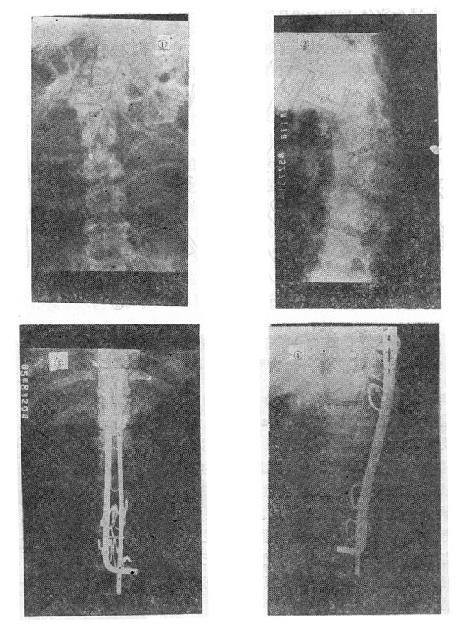

(三)爆裂型骨折的治疗 如不合并严重的神经系统症状,损伤又在两周以内者,可以用双Harrington法,撑开矫正,或用Dick手术;可以获得满意的结果(图73-13)。复位后需融合相邻两个椎间隙,因为CT常显示在爆裂型骨折中,相邻的上、下两个椎间盘均有损伤,如不融合,日后取棍后会出现腰痛。使用本法时,如前纵韧带完整,则很容易恢复椎体前方的高度。但爆裂型骨折存在下述三种情况时,需行前路减压术:①合并神经系统症状较重者;②就诊较晚,已两周以上者(常常10天以上就复位比较困难);③脊柱CT扫描显示已有较大的骨折片突出椎管内,使髓腔管变窄超过30%以上者,预示后纵韧带已有明显损伤,使用后路手术方法已无法使骨折片复位。Kostuik复习了日本和多伦多治疗脊柱骨折的结果后证实,前路减压术能使膀胱、肛门及肢体功能得到更好的恢复。

图73-13 爆裂型骨折的治疗 ①术前,骨折脱位;②术后,侧位;③术后,正位